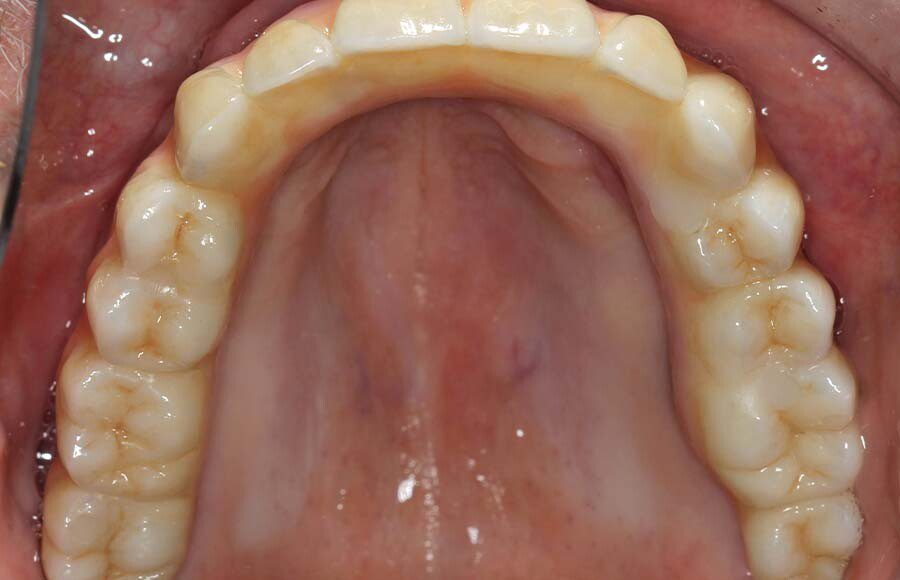

Occlusal (mirror) view of the upper implants. This patient had good bone in these five areas. If the bone was better we would have added a sixth implant.